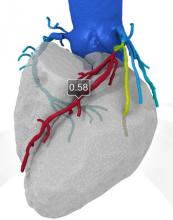

Trends and new technology for cardiac computed tomography angiography (CCTA) were highlighted during the 2012 Society of Cardiovascular CT (SCCT) annual scientific meeting in July in Baltimore, Md. Major topics included the development of fractional flow reserve (FFR)-CT imaging, perfusion imaging, imaging for transcatheter aortic valve replacement (TAVR) and analysis software advancements.